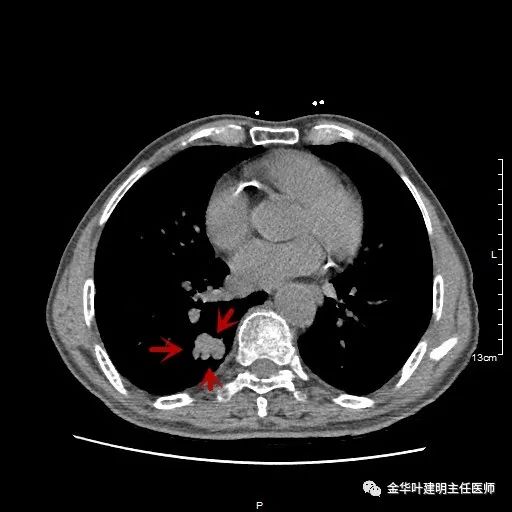

以上示右肺中叶病灶3。是混合磨玻璃结节,位置差,邻近肺门部,无法局部楔形切除,抗炎治疗后靶扫描显示了更清楚的细节,是典型的肺癌影像特征(此处未另提供)。从单病灶来看,需要行右肺中叶切除并清扫淋巴结才能得以治疗。

以上示右中叶病灶4。也是囊腔型病灶,病灶大,囊壁是磨玻璃密度,亦是较为典型的囊腔型肺癌影像。单病灶看,需中叶切除来治疗,因病灶3的存在,中叶切除可同时解决病灶3与病灶4。